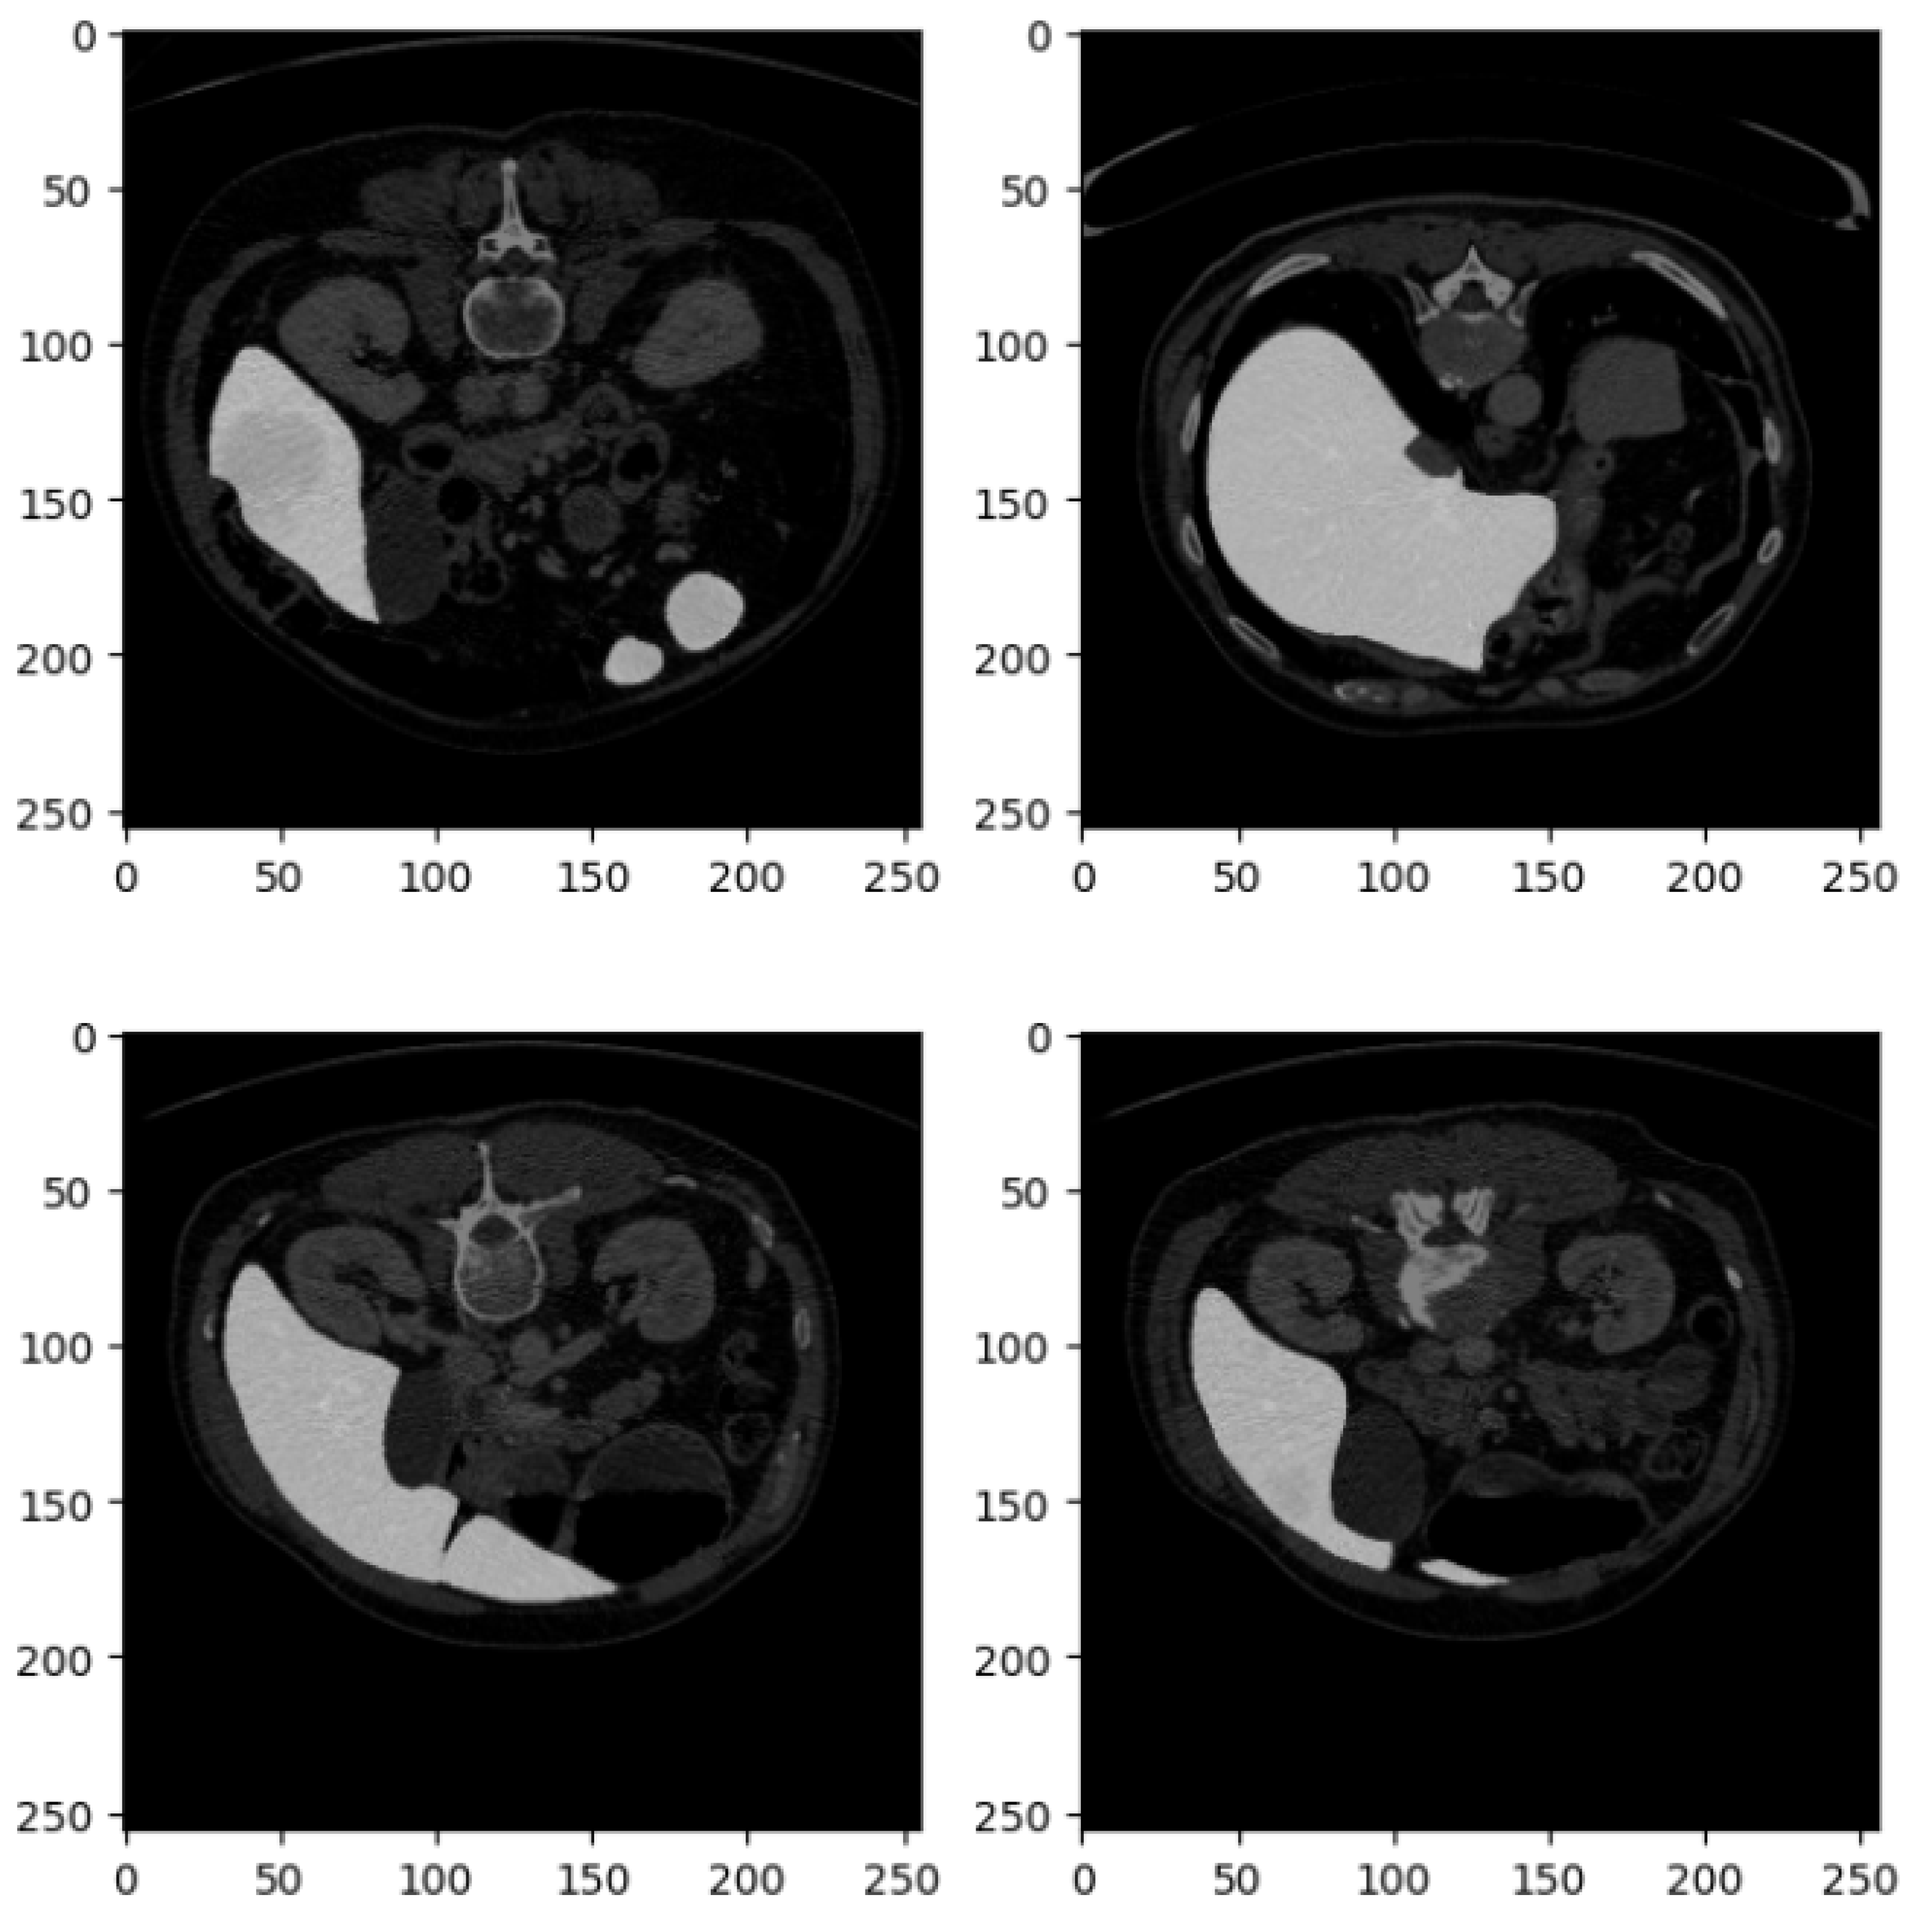

Figure 3 shows four related examples of CT liver images belonging to the DII dataset.

Figure 3, similar to Figure 2, consists of four axial slices from a CT scan, each displaying different cross-sections of the abdominal region. These images are part of the DII dataset, and their detailed description is as follows:

The set is arranged in a 2 × 2 grid of square images, each with a resolution of 250 × 250 pixels, consistent with the format in Figure 2. Like the previous set, these CT slices are taken from the axial plane, providing horizontal cross-sections of the abdomen at varying anatomical levels.

In the top left slice, portions of the kidneys are visible, with the left kidney prominently displayed. Sections of the gastrointestinal tract are also identifiable, and the spine is centrally located, providing a clear view of the vertebral body. The top right slice captures part of the liver on the left side, the spleen on the right side, and some sections of the bowel. The stomach may also be visible, depending on the level of the scan. The bottom left slice offers a clearer view of the left kidney, with the vertebra still centrally located. This slice also provides a good view of the posterior abdominal wall and adjacent structures. In the bottom right slice, both kidneys are distinctly visible, and the spine remains centrally located. The intestines and surrounding tissues are also identifiable in this view.

These images are likely contrast-enhanced, as evidenced by the bright areas, particularly in the liver, kidneys, and gastrointestinal tract, indicating high contrast uptake in these organs and their vasculature. The soft tissue structures are well differentiated due to the contrast, while bone structures, such as the vertebrae, are clearly visible. The grayscale intensities across the images show excellent contrast resolution, which allows for clear differentiation between muscle, fat, organs, and bone.

These slices provide valuable insight into the spatial relationships of major abdominal organs, with the kidneys and liver being especially prominent. This suggests that the images may be focused on assessing the function or structure of these organs. The visibility of the vertebrae in all slices also enables an assessment of the spine in the abdominal context. The images are likely used for diagnostic purposes to assess conditions such as kidney abnormalities (e.g., hydronephrosis or masses), liver conditions (e.g., hepatomegaly or lesions), or bowel issues (e.g., blockages or inflammation).

These slices provide a detailed look at key abdominal organs and would be useful for clinical diagnostics or anatomical study, given the high contrast and clear visualization of both soft tissues and bone structures.